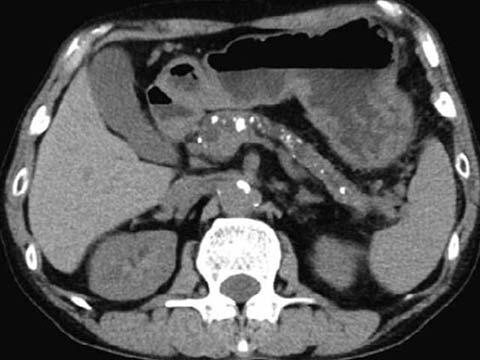

国試過去問解説 慢性膵炎(112A73)